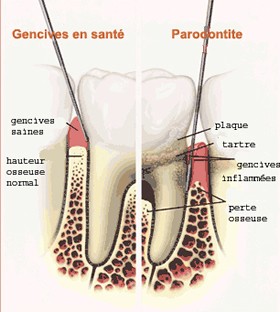

Le principal problème buccodentaire chez l'adulte concerne, outre la carie, les maladies parodontales (maladies de la gencive).

Lorsqu'on sait que les maladies parodontales touchent 80% des adultes, une bonne hygiène dentaire est indispensable.

Le signe majeur est une inflammation des gencives dû à l'accumulation de plaque dentaire et de tartre.

La plaque dentaire est composée d'éléments de la salive, de bactéries ainsi que de débris alimentaires. Lorsqu'elle n'est pas retirée à l'aide d'une brosse à dent et du fil dentaire, la plaque se durcit et se transforme en tartre.